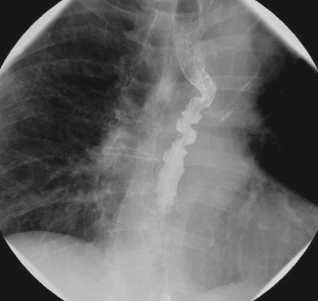

Corkscrew Esophagus Radiology Case Radiopaedia Org

Corkscrew Oesophagus A Rare Cause Of Dysphagia Eurorad

Diffuse Esophageal Spasm Cirugia Espanola English Edition